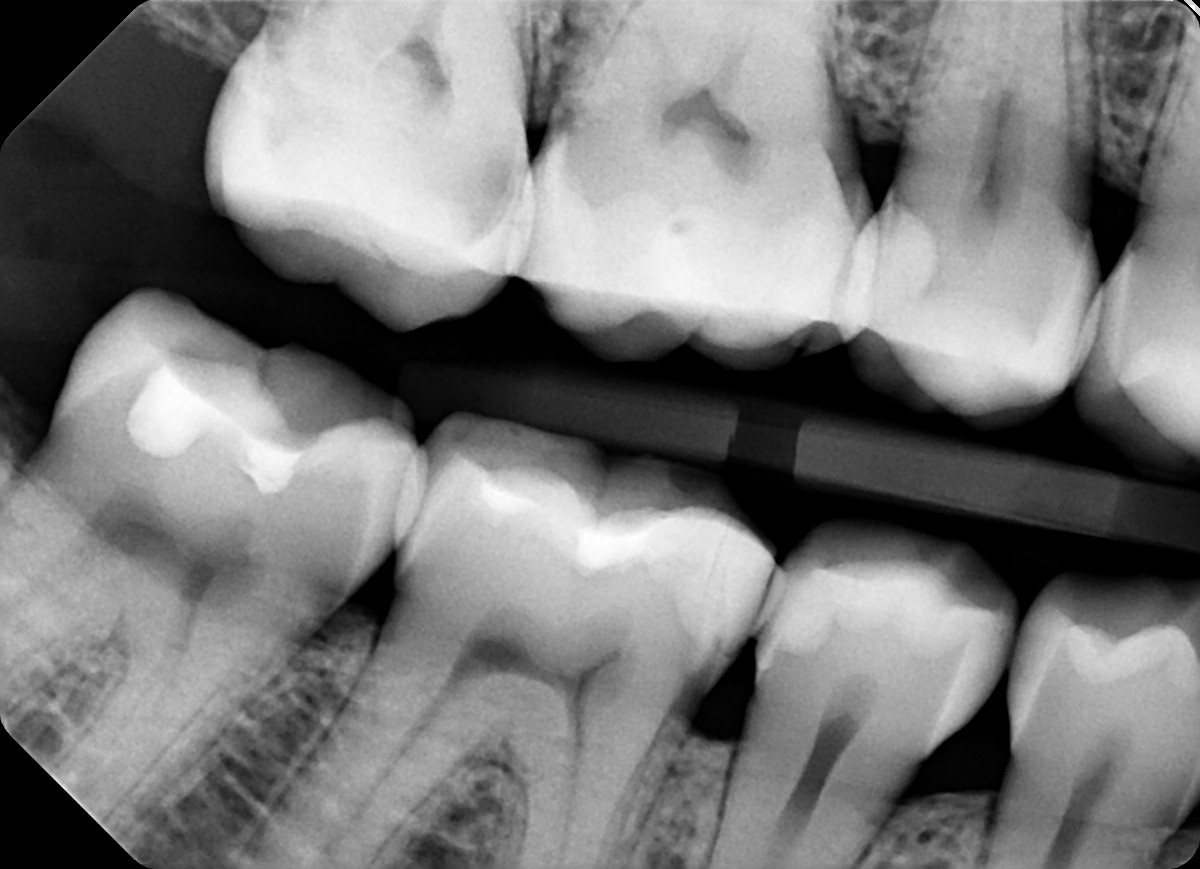

11. On which surface a recurrent caries can be detected?

12 / 35